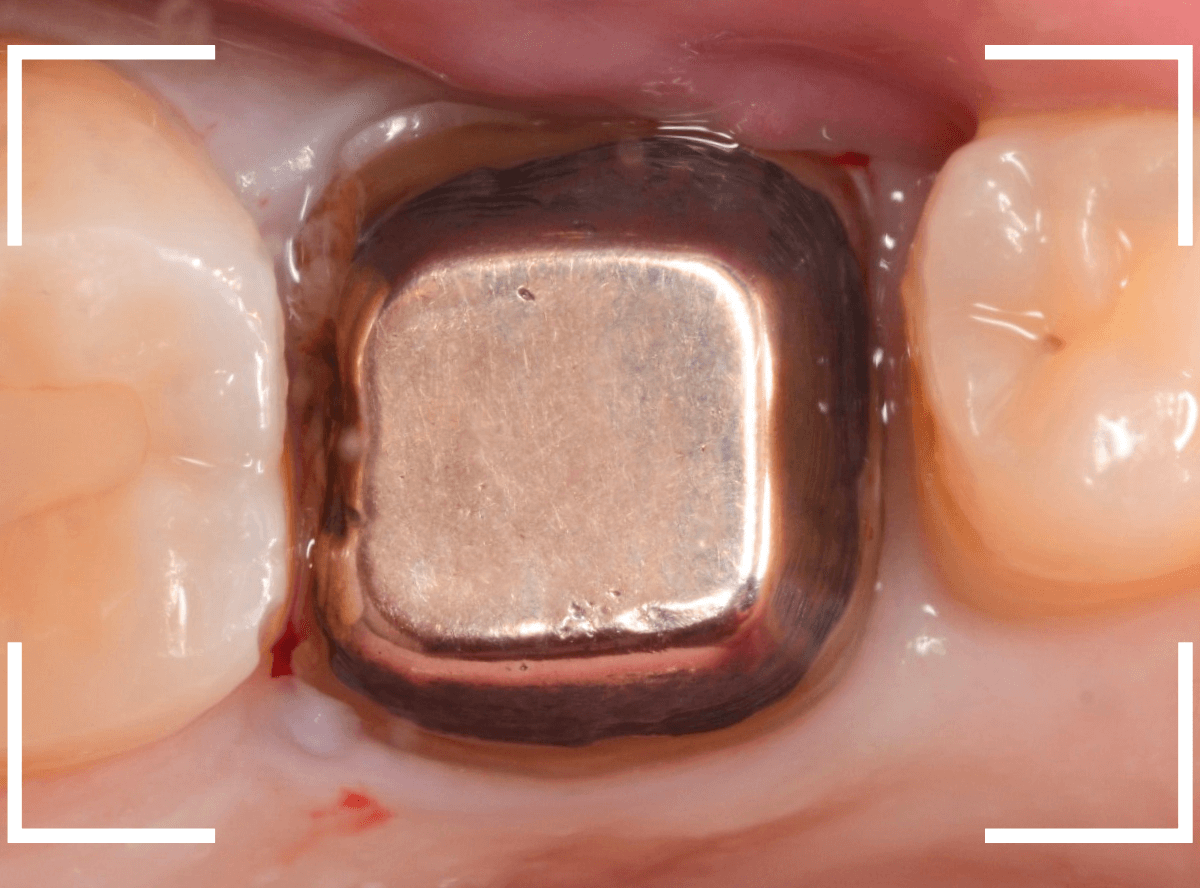

Case.1

こちらは比較的簡単な歯の土台の再治療のケースです。

下の奥歯の虫歯の治療後に、金属の土台(メタル・コア)をsetして、長期間放置してしまいました。

見た目的にはあまり問題なさそうにみえましたが、奥歯との間の歯肉が若干炎症気味でぶよぶよしてるのが気になりました。